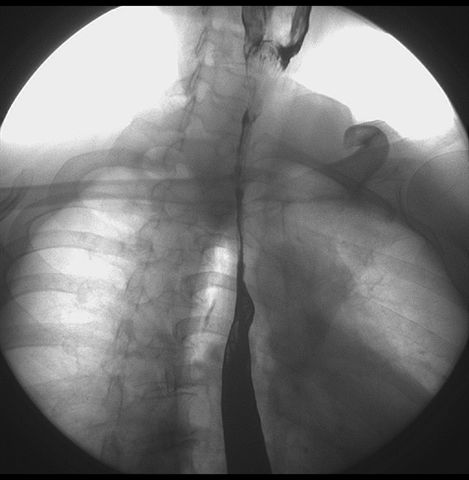

标题: X6872:F,69y,胃部不适。

瀑布型胃,胃粘膜那是一个乱,窦部充盈不好,第16幅窦部粘膜反倒又很顺,先定个胃炎胃窦炎胃窦癌待排之类,建议进一步作胃镜检查。

北京肿瘤医院胃镜诊断皮革胃。